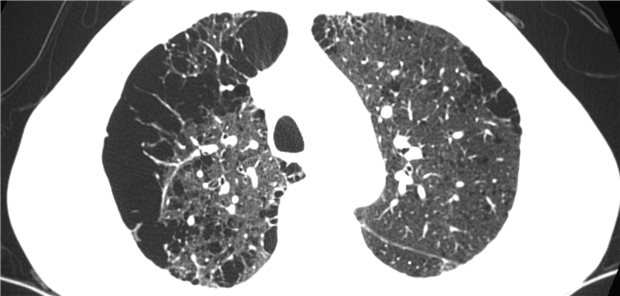

Tobias Barton, Universitätsklinikum Heidelberg, Forschungsgruppe stereotaktische und räumlich fraktionierte Radiotherapie, untersuchte mit einer multizentrischen Studie eine MR-geführte, adaptive Radiotherapie bei Patientinnen und Patienten mit lokal fortgeschrittenen Bronchialkarzinomen.